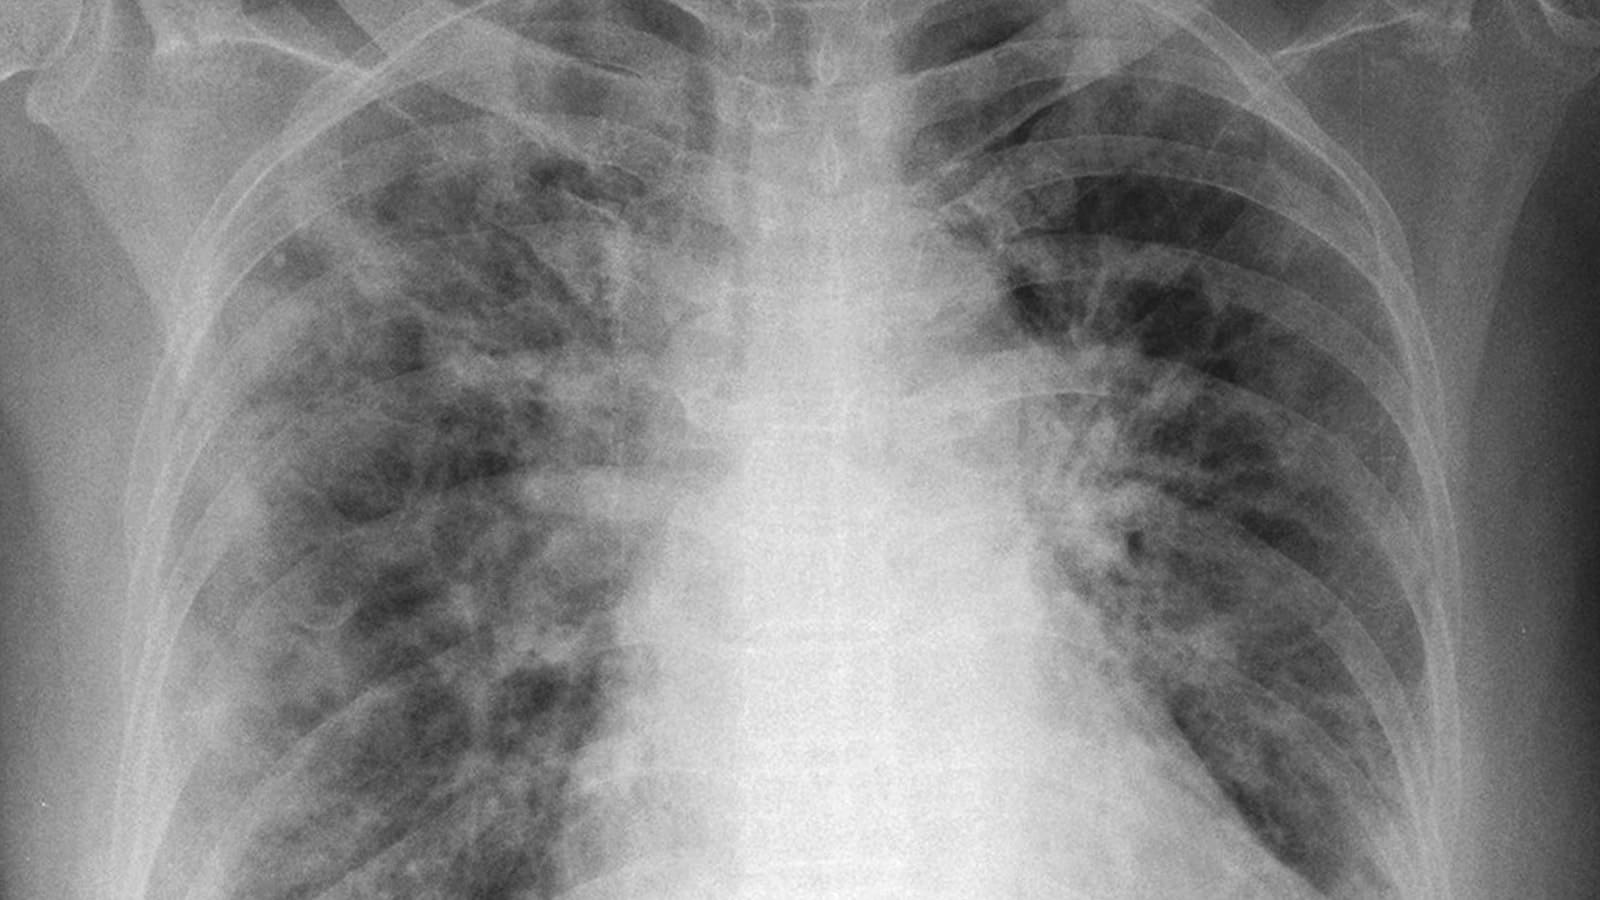

While current differentiation methods involve expensive and time-consuming procedures, such as computed tomography (CT) scans, Fleischer’s machine learning model looks at a simple X-ray image and finds patterns that are too subtle even for the expert human eye. This tool would give doctors a new measure for determining the type and severity of COVID-19 pneumonia. And the process, on the ground, is simple.

Fleischer and graduate student Mohammad Tariqul Islam posted a paper detailing their work on medrxiv (pronounced med archive), a server for scientists to share results in the form of early drafts while a paper undergoes the formal editorial process. At the time of this writing, Fleischer’s paper “Distinguishing L and H phenotypes of COVID-19 using a single X-ray image” has not yet been peer-reviewed.

Gattinoni has said that CT scans are currently the best way to reveal the lung patterns of the disease. But CT scans, which combine many X-ray images from multiple angles into a single picture, are time-consuming and very expensive. Even in well-heeled hospitals, the scanning procedure takes time to schedule and perform. For viral patients, transport to a tomography facility is hazardous both to them and to staff. When human resources are strained, as they have been in hospitals from Queens to Jakarta, these procedures are taxing. In many rural or developing areas, CT is simply not an option.